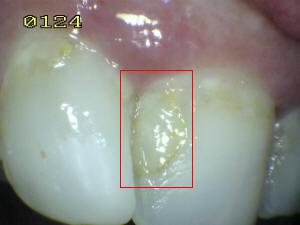

¿Determine los códigos pertinentes a cada imagen?

Click en el hipervínculo: Para comparar el resultado de su diagnóstico